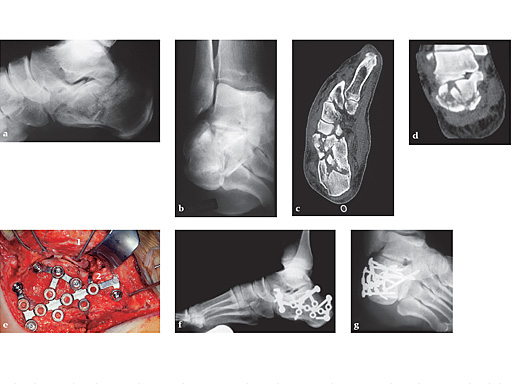

First clinical use (January 4, 2000, Dresden) of the new interlocking calcaneal plate in a B2 fracture of the calcaneus

The lateral view and the Brodns view show the deep impaction of the posterior facet (see Fig a-b).

The axial and coronal cut of the CT scan show the severe damage to the calcaneo-cuboidal and subtalar joint classified according to the new AO-Classification as 81.2 B2 [ie, (1.3.3)]. 81.2 = calcaneus, B2 = intraarticular fracture of two joints involved, d = posterior facet, h = cuboidal facet, 1.3.3 = bony lesion, multifragmentary, severely distocated (see Fig c-d).

Intraoperative situation after anatomical reduction and fixation with the interlocking plate. 1 = one of the four 2.0 mm K-wires, which are inserted in the talus and cuboid keeping the full thickness flap upwards for optimal exposure. 2 = tab bowed close to the bone in the calcaneal neck area to keep the ante (see Fig e-g).